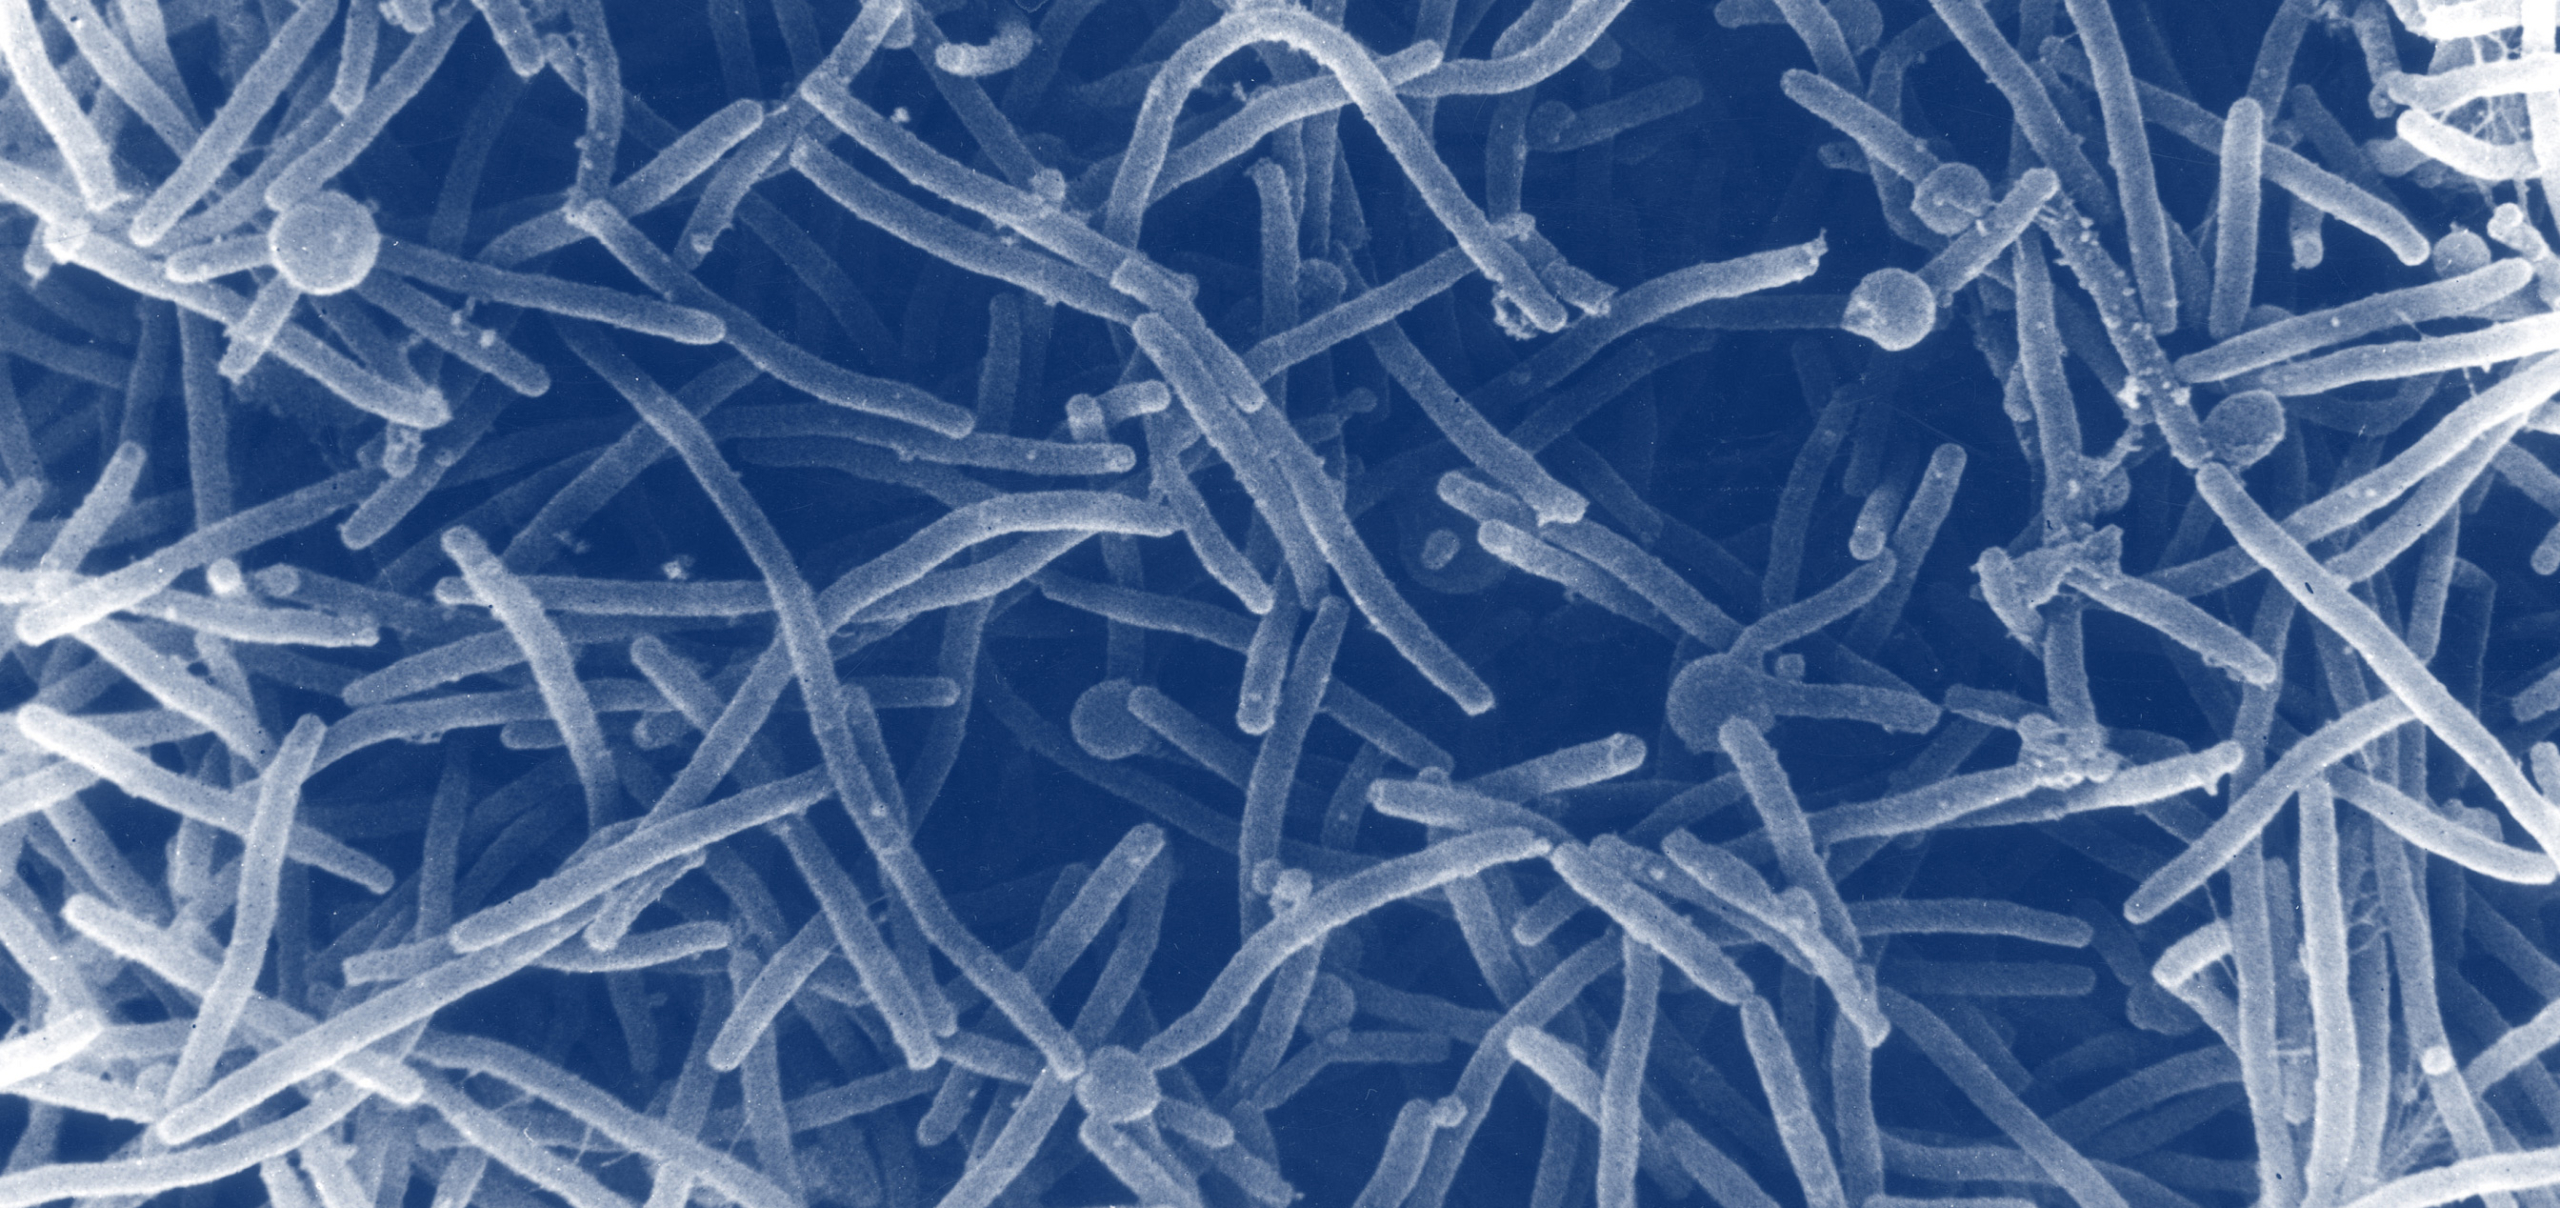

The cause (and oftentimes, the cure) of many vaginal infections lies in the vaginal microbiome (VMB). Just like your gut, your vagina is home to an ecosystem of microscopic residents. Ideally, these microbial communities protect the vaginal environment from invaders.1

Throughout your life, the microbes residing in your vagina will shift. These changes in VMB composition are common, normal, and not at all “your fault.” Everything from your menstrual cycle to your pregnancy status to the types of period and personal care products you use can alter the composition of your VMB, at least temporarily.2,3 Oftentimes, these fluctuations are unnoticeable, but sometimes, they can lead to a microbial imbalance or decreased ability to fight off infection.

In general, there are two categories of infections that can impact vaginas. The first is an imbalance in the microorganisms that naturally populate the vagina, which can cause (extremely common and not at all shameful) issues like BV.

It’s estimated that nearly one-third of reproductive-aged women have BV at any given time—meaning women are more likely to have BV than have blue eyes in this country.4,5 BV occurs when microorganisms that are typically less abundant in the VMB, such as Gardnerella vaginalis, Atopobium vaginae, or Ureaplasma urealyticum, grow to become more prominent than protective bacterial species like Lactobacillus.4,6

BV is usually accompanied by a shift in the pH level of the vagina. Ideally, the VMB maintains a moderately acidic vaginal environment (between 3.8–5.0 during non-pregnant reproductive years), which is optimal for keeping potentially harmful bacteria at low levels. However, when BV occurs, vaginal pH becomes less acidic, creating an opportunity for pathogens to grow and thrive.7

Once Chlamydia trachomatis enters the body, it adheres to and penetrates cells lining the vagina, where it can evade immune attack and replicate. Vaginal microbiomes that contain species of bacteria such as Lactobacillus crispatus and Lactobacillus jensenii have been shown to actively protect against chlamydia infection, likely due to the forms of lactic acid they produce.9